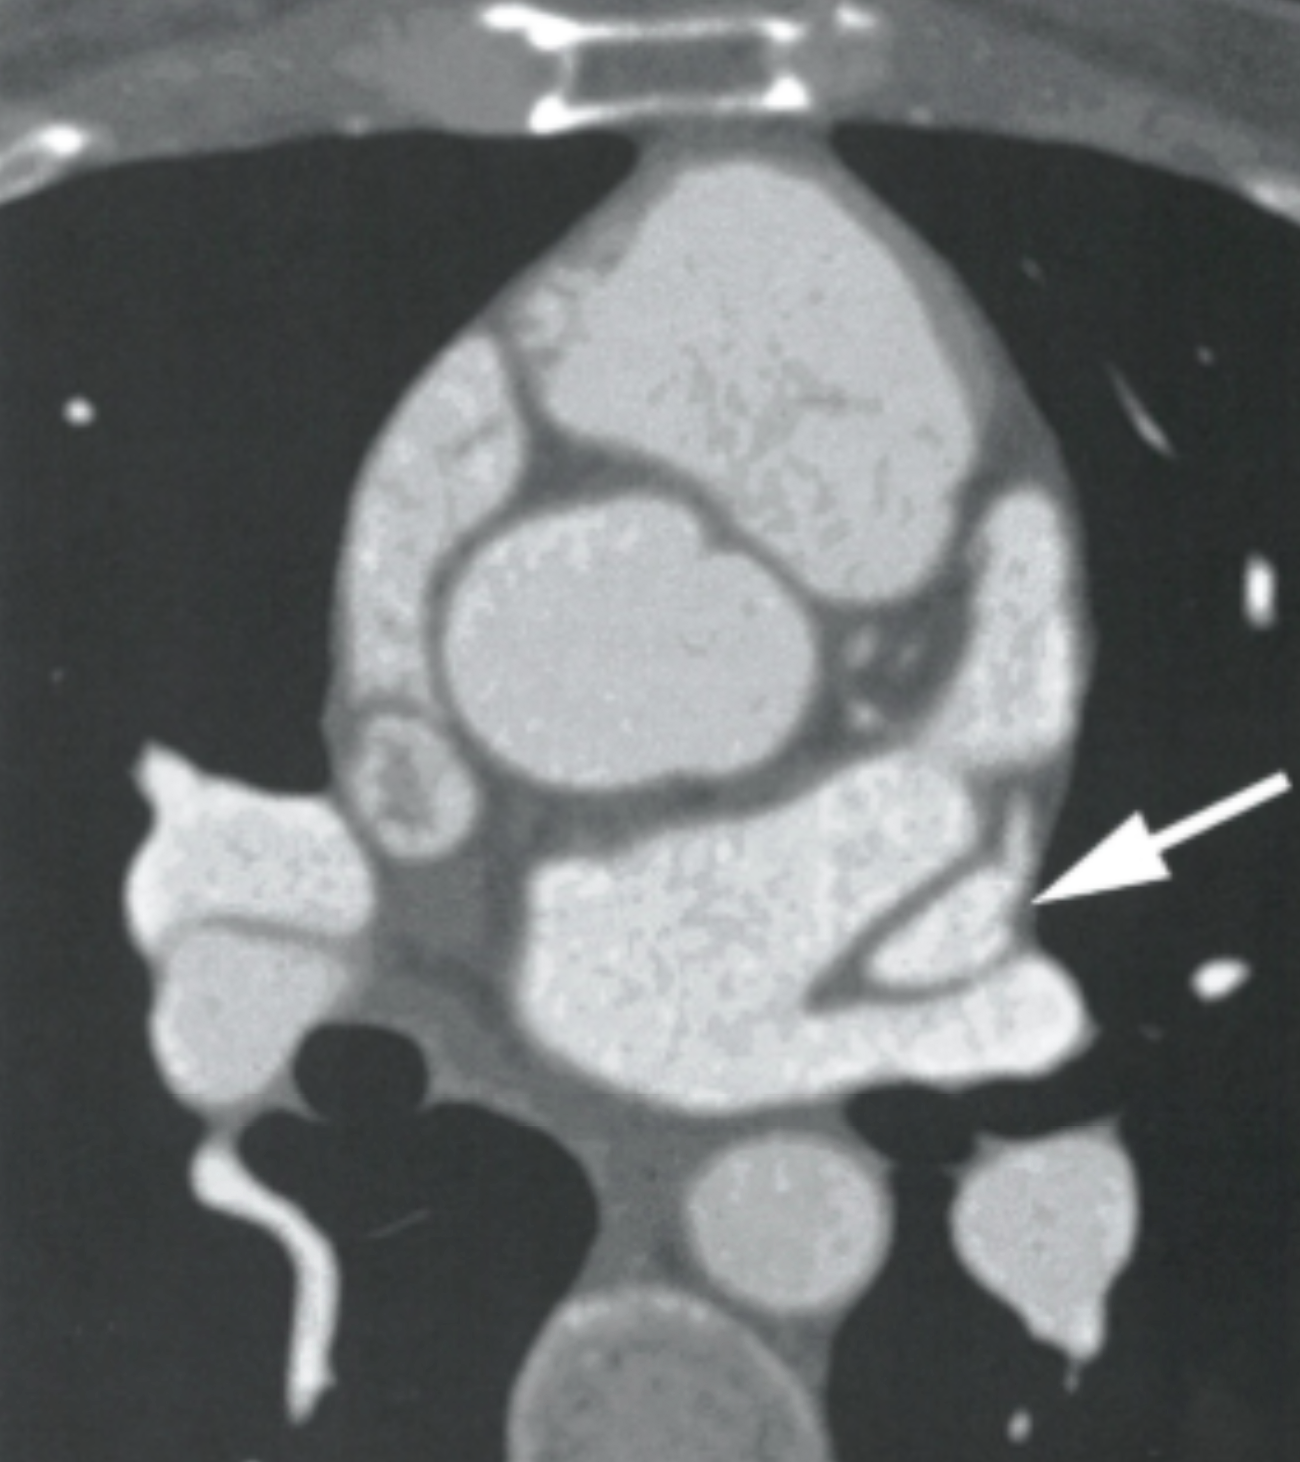

Describe the findings

Congenitally BAV